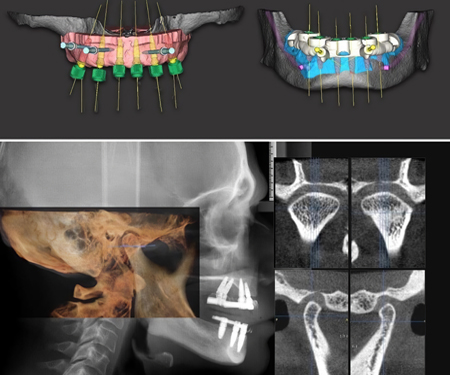

数字化修复

数字化